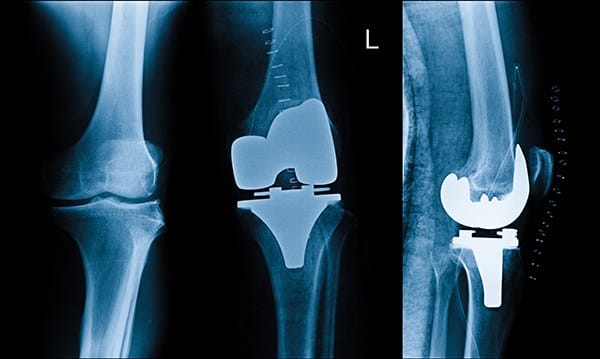

عملية تغيير مفصل الركبة

في البداية، من المهم توضيح أن عملية تغيير مفصل الركبة هي إجراء جراحي يستبدل فيه المفصل التالف بآخر صناعي مصنوع عادة من خليط من المعدن والبلاستيك الطبي يطلق على هذا الإجراء أيضًا “استبدال الركبة بالكامل” أو “استبدال جزئي”، بحسب درجة التلف الحاصل في المفصل، ويهدف هذا الإجراء إلى:

أولًا: الاستبدال الكامل لمفصل الركبة

يعتبر هذا النوع الأكثر شيوعًا، خاصة لدى المرضى الذين يعانون من خشونة شديدة أو تلف واسع النطاق في المفصل، في هذا الإجراء، يقوم الجراح بإزالة كافة الأجزاء التالفة من المفصل، بما في ذلك نهايات عظم الفخذ والساق، ويستبدلها بمكونات صناعية مصنوعة من خليط معدني وبولي إيثيلين عالي الجودة.

يتم تصميم المفصل الصناعي بعناية ليلائم الحركة الطبيعية للركبة قدر الإمكان، ما يمكن المريض من استعادة القدرة على المشي والحركة دون ألم، يوصى بهذا النوع في الحالات التالية:

ثانيًا: الاستبدال الجزئي لمفصل الركبة

يعد الاستبدال الجزئي خيارًا مناسبًا عندما يكون التلف محصورًا في جهة واحدة فقط من الركبة، سواء كانت الجهة الداخلية أو الخارجية، في هذه الحالة، يتم استبدال الجزء المتضرر فقط، بينما تترك بقية مكونات المفصل السليمة كما هي، حيث يمتاز هذا النوع بعدة مزايا: